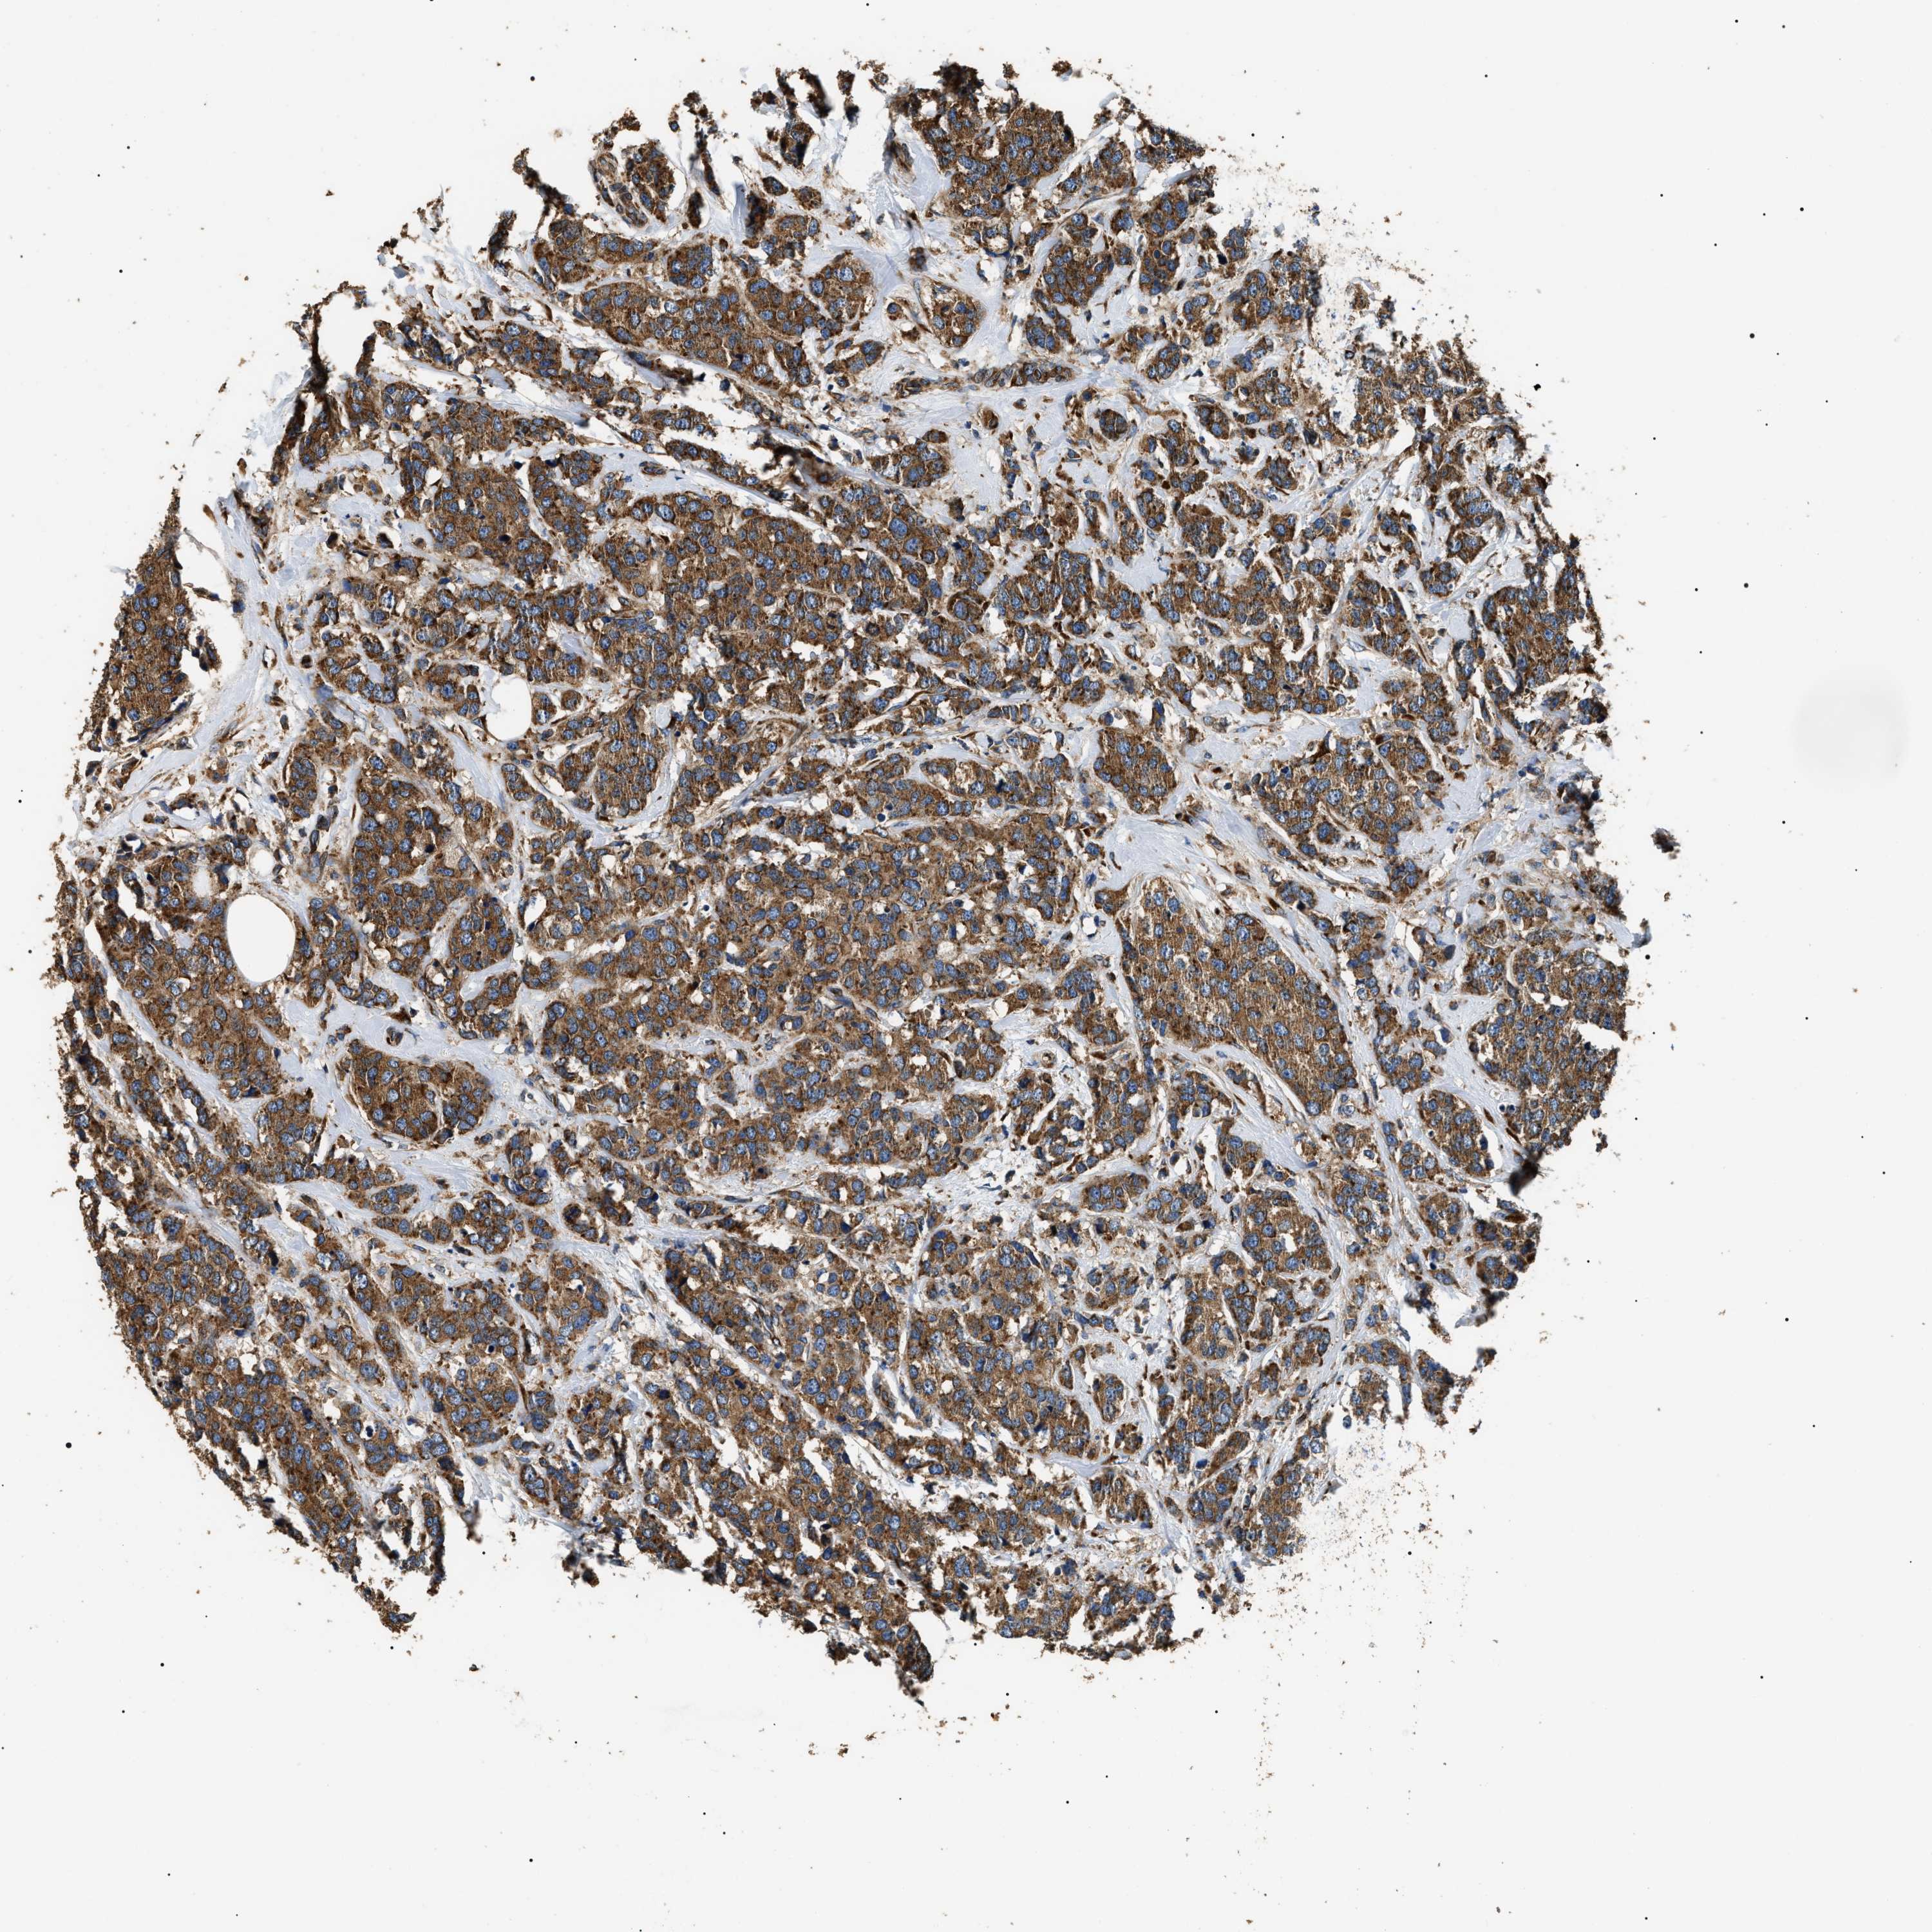

CANCER BREAST CANCER Show tissue menu

BRCA TCGA BRCA VALIDATION PROTEIN EXPRESSION